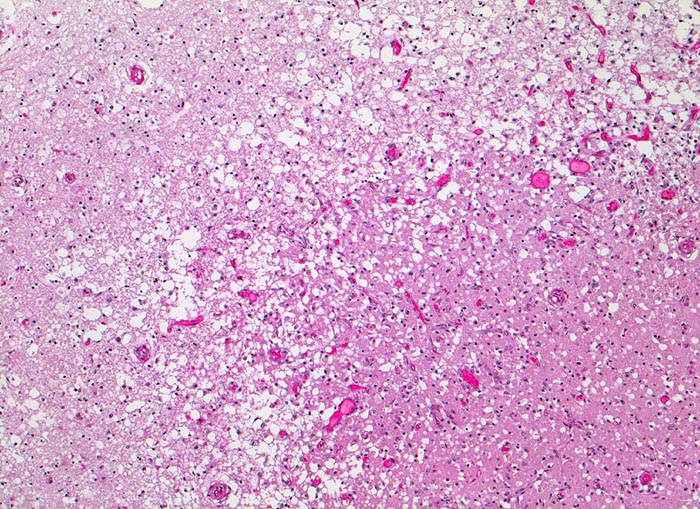

AP/ Anämischer Hirninfarkt

Anämischer Hirninfarkt

• Resorption und Abräumung (ab 5. Tag, vorliegender Fall): Mit zunehmendem Alter des Infarktes wird das Gewebe weicher und zerfällt innerhalb einiger Wochen zerfliessend kleinzystisch (Kolliquationsnekrose). Mikroskopisch ab dem zweiten Tag Auftreten von Makrophagen im Randbereich. Durch Phagozytose von Myelinbruchstücken lipidhaltige Vakuolen im Zytoplasma der Makrophagen (=Fettkörnchenzellen). Nervenzellen im Randbereich der Nekrose können das Bild einer ischämischen Schädigung zeigen (Hypereosinophilie). Gefässproliferation. Perifokale Gliose.

• Links unten leptomeningeale Gefässe mit partiell rekanalisierten alten thromboembolischen Verschlüssen.

• Unscharfe Mark-Rindengrenze im Bereich der nekrotischen Rinde.

• Spongiotische Auflockerung der Hirnrinde (hellere Areale).

• In der Hirnrinde sind hypereosinophile nekrotische Neuronen mit stark abgeblassten Zellkernen erkennbar.

• Perivaskuläre Ansammlungen von phagozytierenden Fettkörnchenzellen mit reichlich lipidhaltigem Zytoplasma und ovalen Kernen sowie wenige extravasierte Erythrozyten.